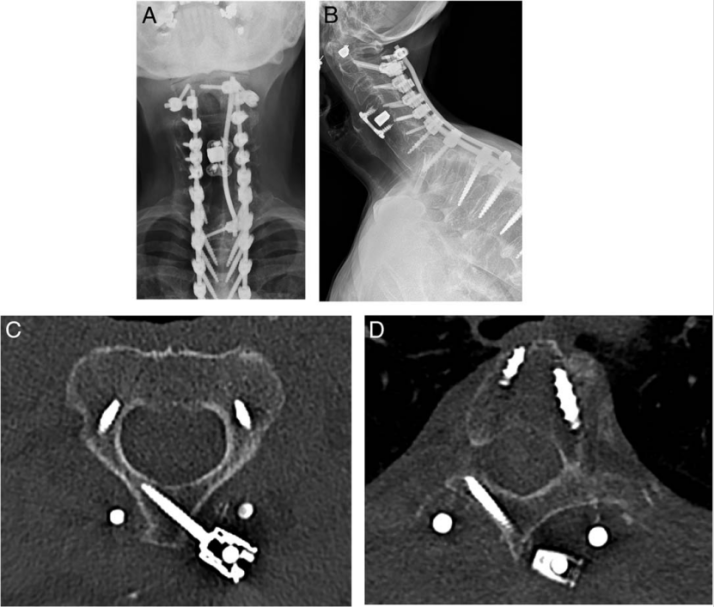

这种**化固定点的原则也可应用于颈椎,尤其在C2节段增加锚定可提高内固定系统刚度并减少机械应力。在远端,可通过上胸椎节段的经椎板螺钉实现类似的强化效果。在临床实践中,我们常采用C2经椎板螺钉联合上胸椎经椎板螺钉,通过第三根连接杆提供额外固定和支撑,从而优化接受三柱截骨术的重度骨质疏松症患者的内固定生物力学性能(图 6)。

图 6 一名 75 岁女性,因颈胸段后凸畸形行 T2 椎弓根截骨术。因骨质疏松症,采用第三根棒固定(C2和T3三点固定)以提供额外的后路张力带。术后(A)正位和(B)侧位颈椎 X 线片显示左侧 C2 经椎板螺钉、左侧 T3 经椎板螺钉及跨 T2 椎弓根截骨部位的第三根棒;轴位 CT 图像显示左侧(C)C2 和(D)T3 经椎板螺钉的植入位置。